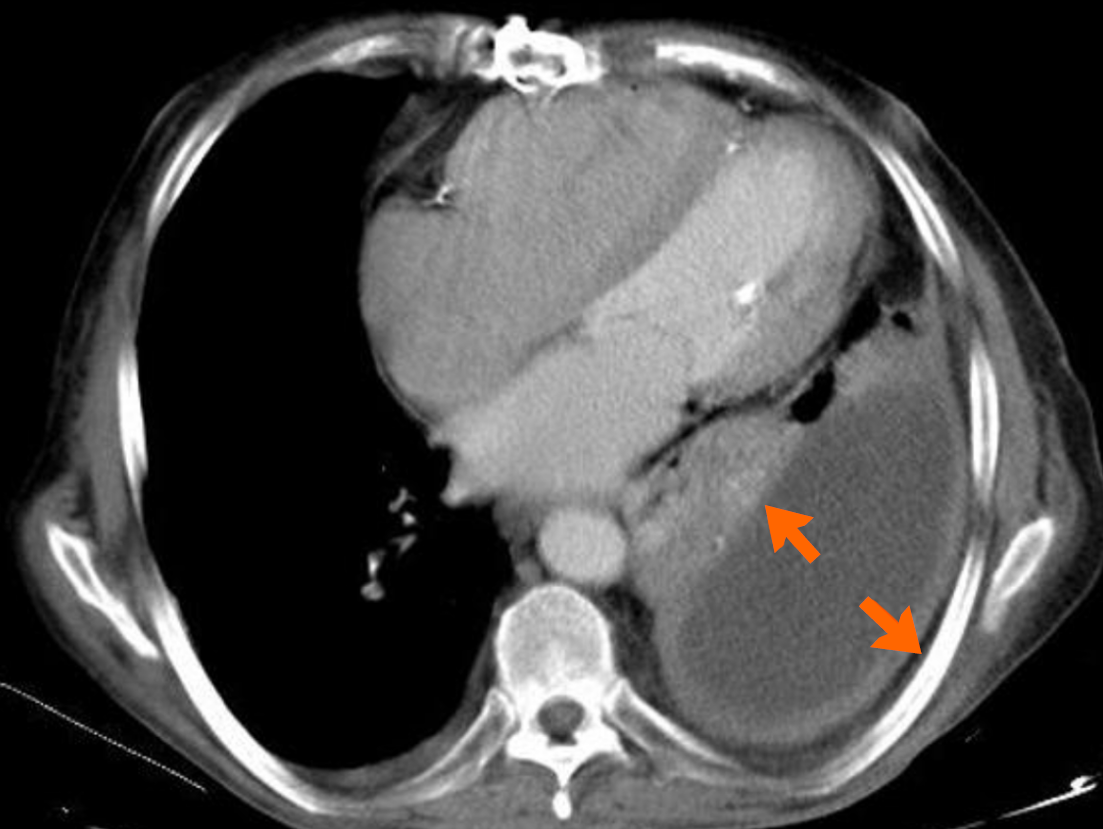

Empyema, or purulent pleural effusion, results from the extension of infection into the pleural space. It is visualized as a complex pleural collection with septations, internal debris, and contrast enhancement of the pleural layers, commonly referred to as the “split pleura sign” (Figure 2)[27,28]. Advanced imaging modalities such as ultrasound and contrast-enhanced CT provide critical information for diagnosis and planning interventions like thoracentesis or chest tube placement. Bronchopleural fistulas, although rare, are serious complications of necrotizing pneumonia[29]. Clinically, they often present with persistent air leaks despite chest tube drainage and are frequently associated with pneumothorax or hydropneumothorax. Recognizing the condition on imaging requires a high clinical suspicion and confirmation typically requires CT[30].

Figure 2

Figure 2 Axial contrast enhanced arterial phase computed tomography image showing the split pleura sign, seen with pleural empyemas refers to the thickening and increased contrast enhancement of the visceral and parietal pleura separated by empyema or an exudative effusion (arrows).